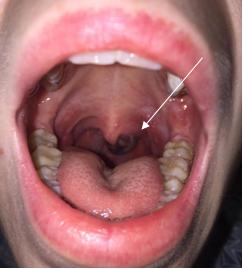

On exam, there was a mass adjacent to the left lateral uvula, approximately 1.5-2 cm in length and 1 cm in width, appearing to originate from the palate. The mass was purple in color with some areas of scattered opacity. Tonsillar pillars and uvula were normal. There was a clear nasal polyp in the anterior left nare. The patient had bilateral submandibular adenopathy.

Figure 1: Oropharyngeal exam

Image Credit: Eric Goedecke, DO |